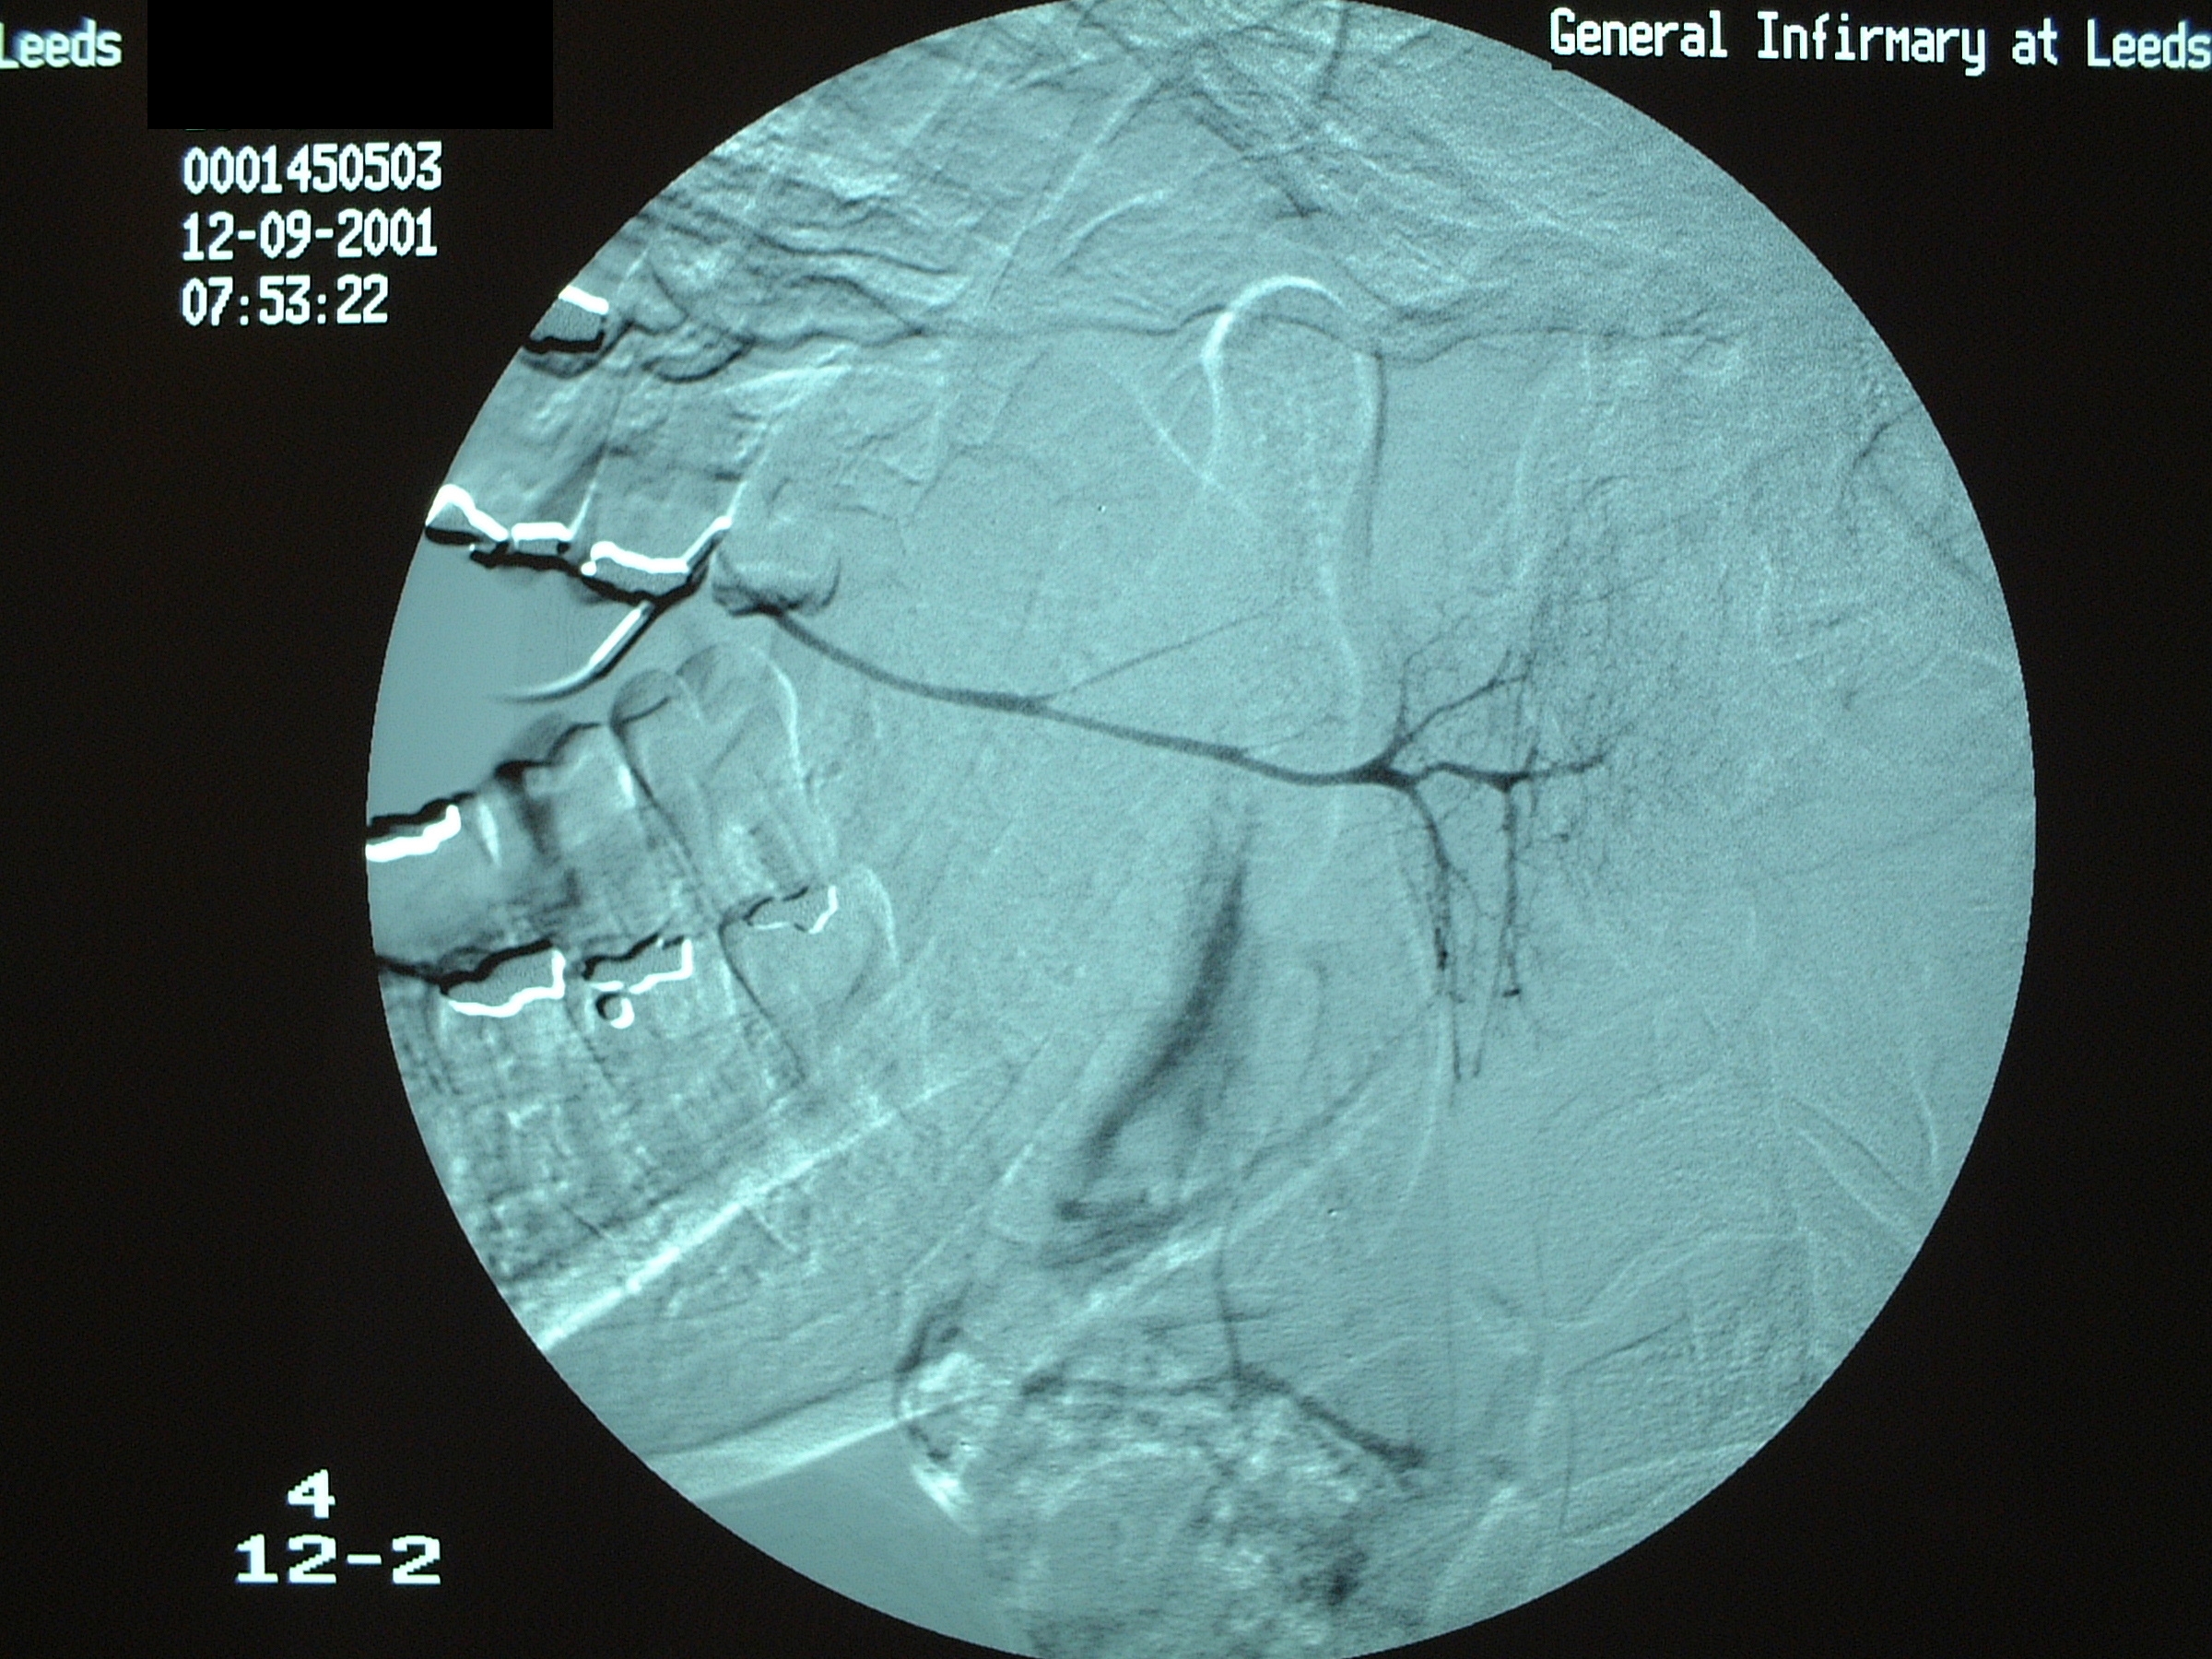

Approximately 80 % of salivary calculi occur in the ductal system of the submandibular glands. This is due to the greater length of the duct, its upward course and the thicker mucus secreted by the submandibular glands. There will usually be a history of painful, recurrent swelling in the submandibular region, particularly associated with eating or the anticipation of eating (pre-prandial swelling). Plain (X-ray) radiography will usually demonstrate a calculus in the duct (see Figure 1), or in the junction of the duct and gland or the gland itself (see Figure 2).

Figure 1: Calculus superimposed on a plain X-ray occlusal view of the anterior (front) floor of the mouth.

In the duct, a calculus is date shaped, at the junction of duct and gland it is comma shaped and in the gland it is round. Should a calculus not be visible on plain X-ray images, a sialogram is required which may demonstrate a radiolucent stone, a mucus plug or a stricture in the duct (see Figure 3).